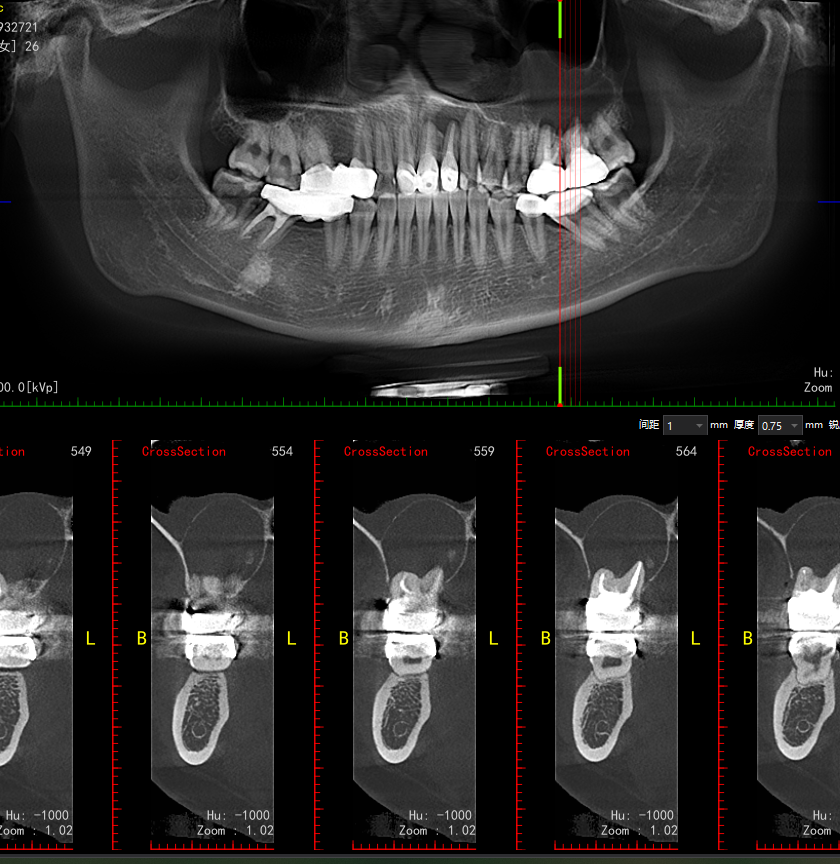

左上后牙区颌骨囊肿与马上要突破上颌窦

年纪轻轻,根管治疗的又一宗罪吧